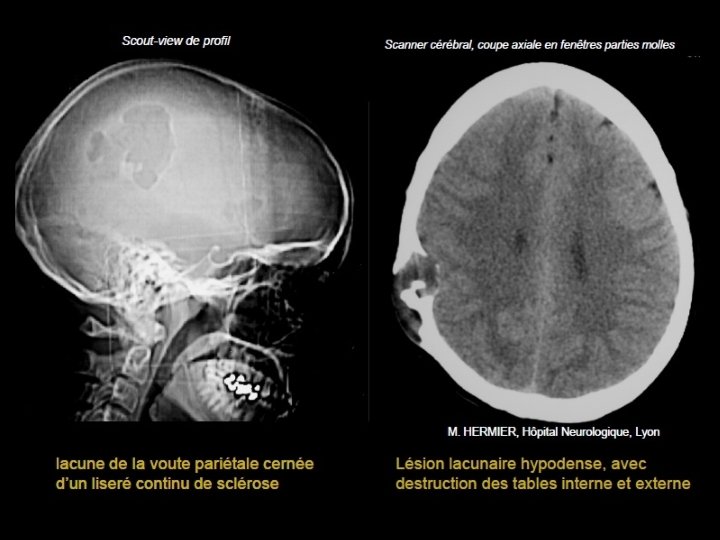

Métastases • Cause la plus fréquente des tumeurs de la voûte • À partir de la 5ème décade • PPRST+++: poumon, prostate, rein, sein, et thyroïde. • Lésions multiples : sein et poumon • Lésion unique, soufflante : rein et thyroïde • Enfant : Neuroblastome étiologies à évoquer en 1 er

• Scanner: - Plus volontiers lacunaires que condensantes. - Initialement diploïques - Destruction secondaire des tables interne et externe - Envahissement des parties molles et de l’espace épidural • IRM - T 1: Hypo ou isosignal effaçant l’hypersignal habituel du diploé, - T 2: Hypersignal - Prise de contraste.